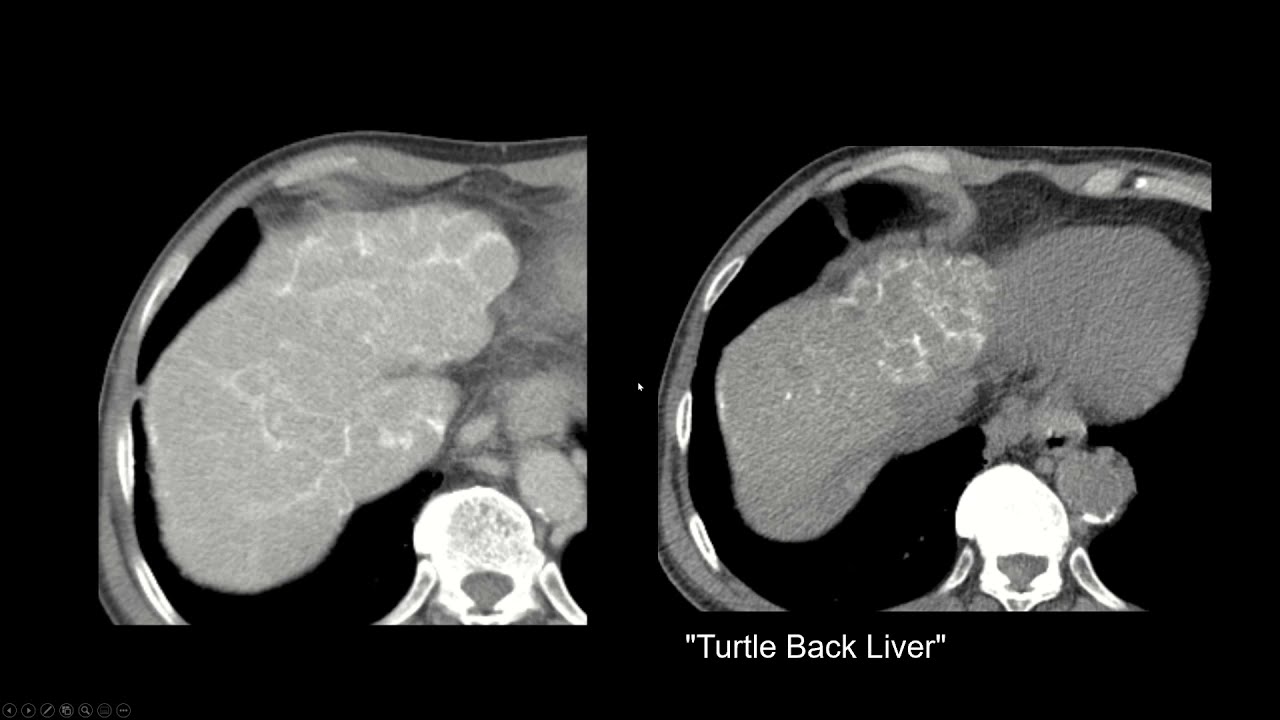

What does CT show in pulmonary fibrosis

Fibrosis is the proliferation of connective tissue with the appearance of scars due to a violation of the mechanisms of healing of the wound surface.

When healing does not proceed properly, scarring may occur, leading to the fact that the organ cannot function fully.

Accordingly, pulmonary fibrosis is a scarring of lung tissue. The number of cells capable of saturating the blood with oxygen decreases. Consequently, respiratory efficiency decreases – respiratory failure develops, leading to intoxication, first with exercise, with aggravation of the course of the disease – at rest, and then – even in sleep. Scar tissue in the lungs not only has reduced functional properties, but also serves as an excellent environment for the development of associated infections, such as bacterial (pneumococcal or staphylococcal) pneumonia.

Pulmonary fibrosis is the outcome of tissue inflammation during interstitial (that is, with damage to the intercellular connective tissue) lung disease. The reasons for the development of such a disease may include lung injuries, high environmental pollution, smoking, inhalation of narcotic substances, mold, organic, asbestos, quartz and coal dust, infectious, autoimmune, viral diseases and their complications – bronchitis, tuberculosis, pneumonia, COVID- 19 and more.

CT diagnosis of pulmonary fibrosis

The gold standard for diagnosing pulmonary fibrosis is high-resolution computed tomography. CT diagnostics of pulmonary fibrosis allows to reliably identify the degree of lung damage, to determine the localization of scar tissue. This diagnostic method is recognized as one of the most sensitive non-invasive methods for detecting pulmonary fibrosis. Thus, comparative studies conducted already in 1990 showed that pulmonary fibrosis using high-resolution computed tomography (HRCT) was detected in 91% of cases and only 39% using chest x-ray.

In the presence of pulmonary fibrosis in a serious stage, a pattern (a term adopted for pathological signs in medicine) is visible on CT scans of the so-called “honeycomb” lung – this condition is visible on scans as the same type of air-containing cysts located in several rows in the affected parts one or both lungs. In the early stages of pulmonary fibrosis, such a picture is not observed, so it was necessary to look for signs on CT that would allow to identify the disease at its onset.

One of these signs was the presence of a “ground glass” pattern in the images – foci of slight compaction of the lung tissue. Also, specific signs of fibrosis in a patient can be detected when performing a CT scan of the lungs with functional tests. So, one of the signs – subpleural enhancement of the peripheral pulmonary interstitium – was previously considered a sign of the absence of pathology. Such changes are almost impossible to track using other methods of hardware diagnostics.

At the moment, the accuracy of CT diagnostic methods is increasing due to the introduction of new research protocols and careful study of the results of numerous studies. At the same time, the leading role in the diagnostic process is assigned to the radiologist, who interprets visible changes as pulmonary fibrosis or its absence. The search for early radiation signs of fibrosing lung disease is a key moment for the timely administration of antifibrotic therapy.

Also, it is multislice CT with the diagnosis made that is used to assess the rate of progression of the disease, identify favorable and unfavorable types of fibrotic changes, the success of treatment and the correct selection of therapeutic drugs.